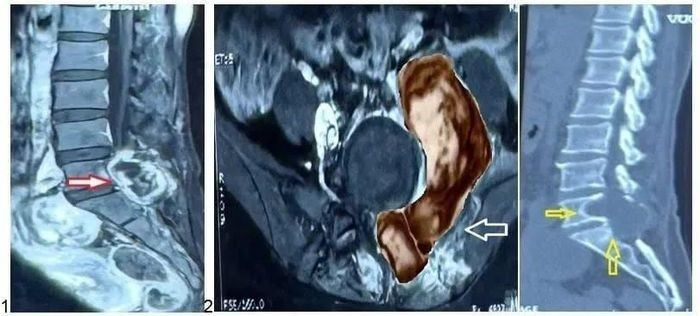

Kết quả chụp MRI tại Bệnh viện Nhân dân 115 cho thấy khối u lớn vùng L5-S1, xâm lấn cơ cạnh sống, cánh chậu và phúc mạc, đúng vị trí phẫu thuật cũ - nghi ngờ ác tính.

Khối u ác tính vùng cột sống thắt lưng của bệnh nhân. Ảnh BV

Kết quả giải phẫu bệnh xác định u bao dây thần kinh ngoại biên ác tính (MPNST) - dạng ung thư hiếm gặp, tiến triển nhanh và tiên lượng nặng. Sau phẫu thuật, bệnh nhân giảm đau, cải thiện vận động. Hiện bệnh nhân đang được điều trị hóa – xạ trị theo phác đồ.